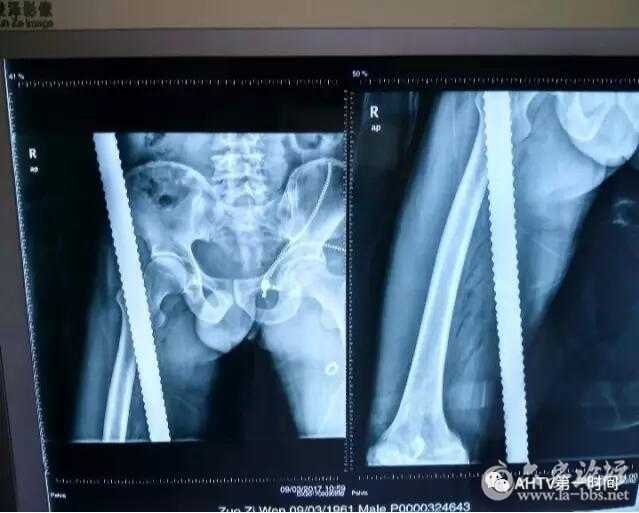

安徽医科大学第一附属医院骨科医师杜公文告诉记者,钢筋从左师傅的髋部,斜穿到大腿的后内侧,没有伤到要害,但是钢筋离他的主动脉和神经是很近的,大概旁开有两公分左右。

安徽医科大学第一附属医院骨科医师杜公文告诉记者,钢筋有一米多长,后来因为离体部太近了,而且又怕在截断的过程中,给病人造成二次损伤,经过充分的考虑,医生就没有给它截断了。

经过医护人员两个多小时的手术,贯穿左师傅腿部的钢筋,被成功取出。安徽医科大学第一附属医院骨科医师杜公文表示,目前来看手术效果是非常成功的,因为目前没有损伤到重要的神经和血管,但是后期的感染,他们还要一边治疗一边观察。